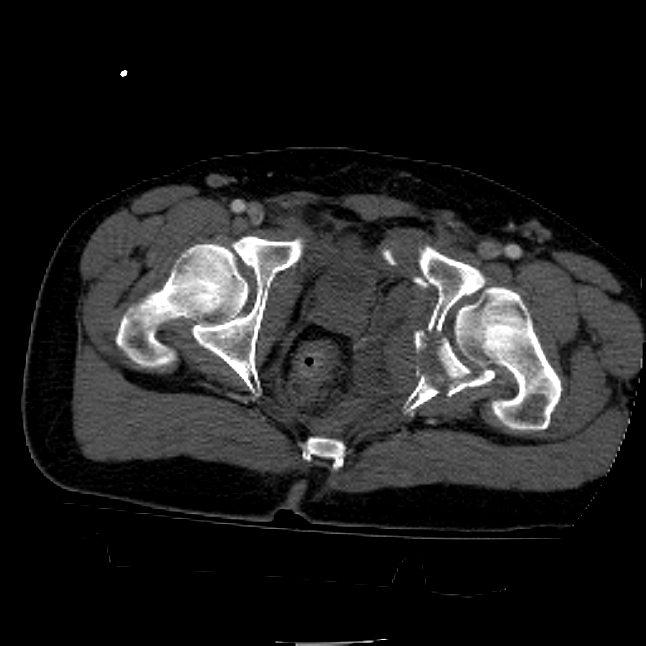

25 yo brittle diabetic, became hypoglycemic and passed out on his motorcycle. Sustained bilateral lateral Hoffa fractures with associated LCL injury on the right and right distal radius fracture. I have questions regarding his pelvic ring/acetabular fracture on the left. Appears to be a very low posterior column fracture with associated posterior wall, marginal impaction. Superior and inferior rami fractures as well on the left giving him a floating segment of inf ramus/ischium/posterior column, but no detectable posterior ring injury. Should the posterior column/posterior wall fracture be addressed surgically because of the marginal impaction? Or is this fracture low enough to be treated non-operatively? I appreciate the input.

It's an interesting case. The plain films show the impaction, but most of the joint looks pretty good. The CT cuts look awful, though.

The impaction is so big I don't think I would ignore it. It IS down low, but it takes up almost the whole southern hemisphere of his joint.